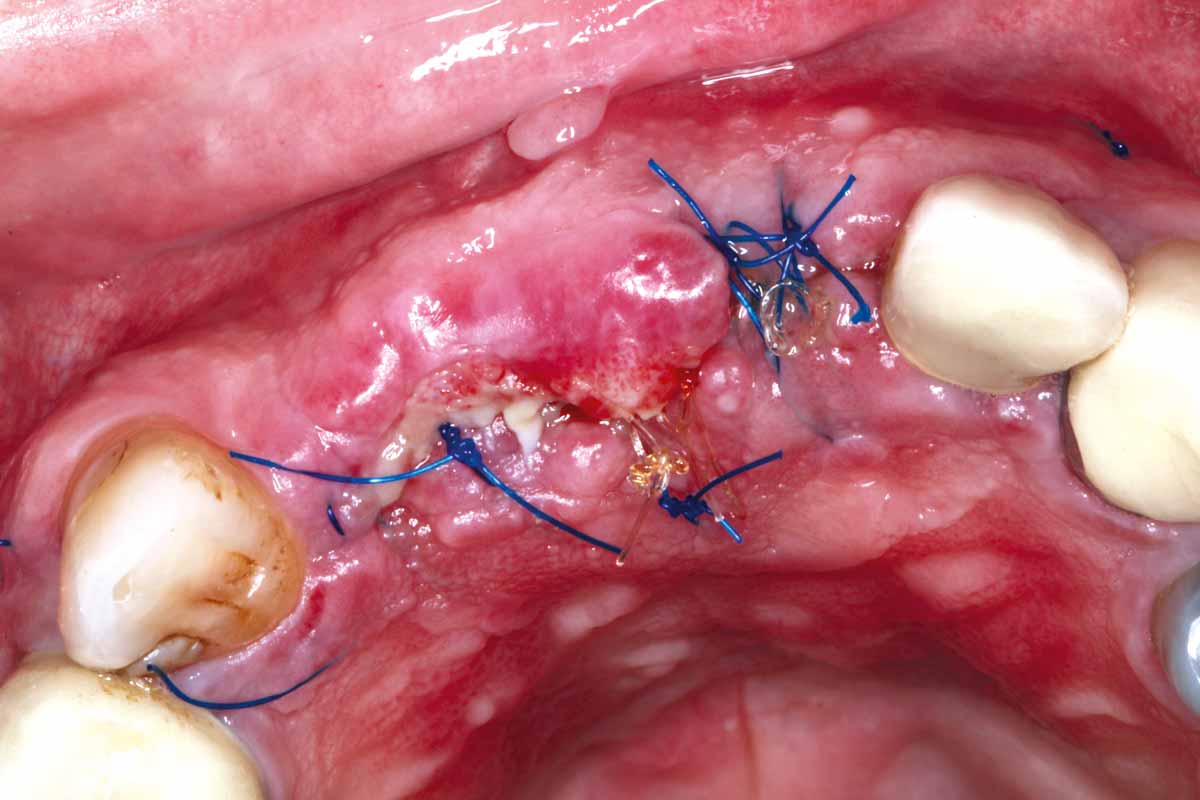

9/27 - GBR with autologous bone chips covered with small particles cerabone® and two mucoderm® used as a barrier membrane

GBR and soft tissue augmentation with cerabone® and mucoderm® - H. Maghaireh & V. Ivancheva

10/27 - mucoderm® was stabilised using titanium pins and sutured together to achieve maximum stability